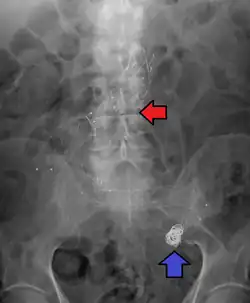

Abdominal aortic aneurysm involves a regional dilation of the aorta and is diagnosed using ultrasonography, computed tomography, or magnetic resonance imaging. A segment of the aorta that is found to be greater than 50% larger than that of a healthy individual of the same sex and age is considered aneurysmal.[9] Abdominal aneurysms are usually asymptomatic but in rare cases can cause lower back pain or lower limb ischemia.

Diagnosis of a ruptured cerebral aneurysm is commonly made by finding signs of subarachnoid hemorrhage on a computed tomography (CT) scan. If the CT scan is negative but a ruptured aneurysm is still suspected based on clinical findings, a lumbar puncture can be performed to detect blood in the cerebrospinal fluid. Computed tomography angiography (CTA) is an alternative to traditional angiography and can be performed without the need for arterial catheterization. This test combines a regular CT scan with a contrast dye injected into a vein. Once the dye is injected into a vein, it travels to the cerebral arteries, and images are created using a CT scan. These images show exactly how blood flows into the brain arteries.[39]